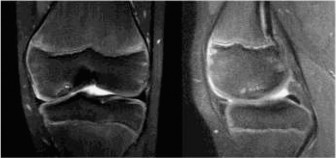

The patient then obtains the following radiograph (Fig. 10–22) which confirms the diagnosis of an OCD lesion of the medial femoral condyle. An MRI is then ordered to examine the lesion further. A T2 image is shown in Figure 10–23.

The correct answer is (C). The patient has an OCD lesion of the posterolateral aspect of the medial femoral condyle which is the most common location for these lesions. Pediatric patients have a much better prognosis for OCD lesions as open distal femoral physes are the best predictor of a successful outcome with nonoperative management. Lesions which have synovial fluid behind the lesion on MRI are potentially unstable and require much more aggressive surgical management to prevent detachment and separation. As this patient is young, has open distal femoral physes, and has no instability on MRI, a trial of conservative treatment is appropriate. Arthroscopic drilling (either antegrade or retrograde) can be performed for stable lesions which have not responded to a trial of conservative management (Fig. 10–24). Open reduction and internal fixation should be reserved for unstable lesions.